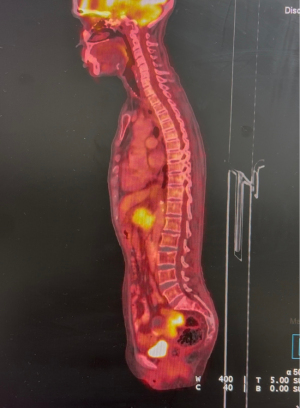

A 62-year-old female presented to gynecology out-patient department (OPD) in March 2025 with complaints of episodic bleeding per vaginum for 6 months (symptoms began around September 2024). It was insidious in onset, gradually progressive and associated with dull pelvic pain and foul-smelling discharge per vaginum. A history of occasional epigastric discomfort with significant weight loss was also elicited. No relevant medical, surgical, family, or personal history was noted. Pelvic examination revealed a 2 cm × 2 cm friable polypoidal growth over the cervical os without parametrial/rectal mucosal involvement. Magnetic resonance imaging (MRI) of the abdomen and pelvis demonstrated an ill-defined soft tissue lesion in the neck & body of pancreas measuring 3.2 cm × 4.2 cm × 3.2 cm, completely encasing the portal, splenic and superior mesenteric veins. Another soft tissue lesion of 2 cm × 2.2 cm × 3 cm was seen in cervical and lower uterine segment without any parametrial extension (Figure 1). Whole body positron emission tomography-computed tomography (PET-CT) scan showed high metabolic activity in the pancreatic and cervical lesions, with no other metabolically active focus elsewhere in the body (Figure 2). Serum carcinoembryonic antigen (CEA) was 22 ng/mL (normal: <3 ng/mL) and carbohydrate antigen 19-9 (CA19-9) was 1,532 U/mL (normal: <35 U/mL). Hemogram and other biochemistry parameters were within normal limits.Endoscopic ultrasound-guided fine needle aspiration cytology from pancreatic mass showed adenocarcinoma with mucinous differentiation (Figure 3). Punch biopsy from cervix was suggestive of adenocarcinoma.